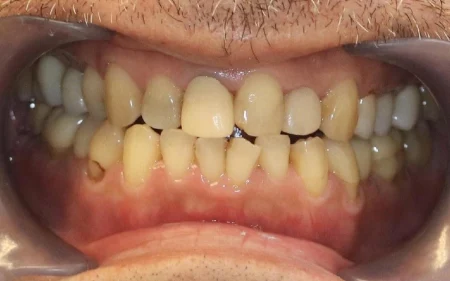

- 当院は、患者様の歯をできるだけ残し、長期的に再治療を防ぎ、質の高い健康を維持することを基本方針としています。

そのため「精密さ・耐久性・生体へのやさしさ」を重視した体制をとっており、原則として自由診療の治療をご提案しています。

一方、自由診療では個々の症例に合わせた治療設計、先進的な材料・技術の使用、再発予防を見据えた治療が可能です。